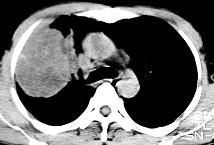

根据所提供的图像,选择最可能的诊断 ( )A.肺内软骨肉瘤B.胸膜间皮瘤C.球形肺炎D.机化性肺炎E.局限性不张

问题 根据所提供的图像,选择最可能的诊断 ( )

选项 A.肺内软骨肉瘤 B.胸膜间皮瘤 C.球形肺炎 D.机化性肺炎 E.局限性不张

答案 A